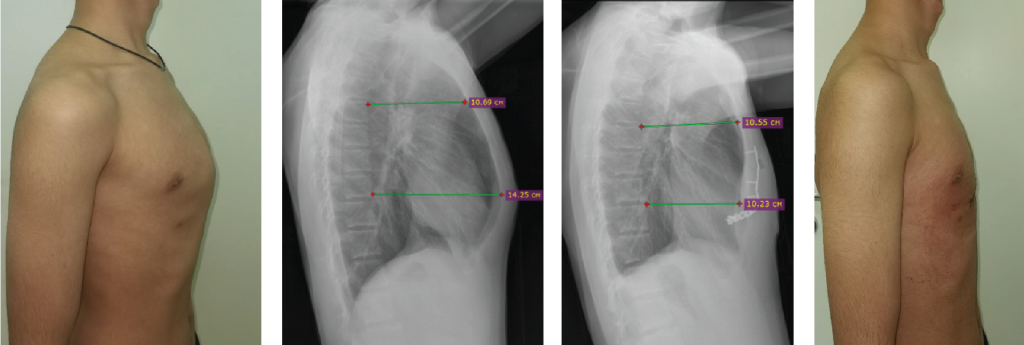

Technical capabilities: minimally invasive and reconstructive surgery technologies, bone plastic materials and instrumental fixation, modern power and ultrasound surgical equipment, navigation, neuromonitoring.

Main areas of surgical work: